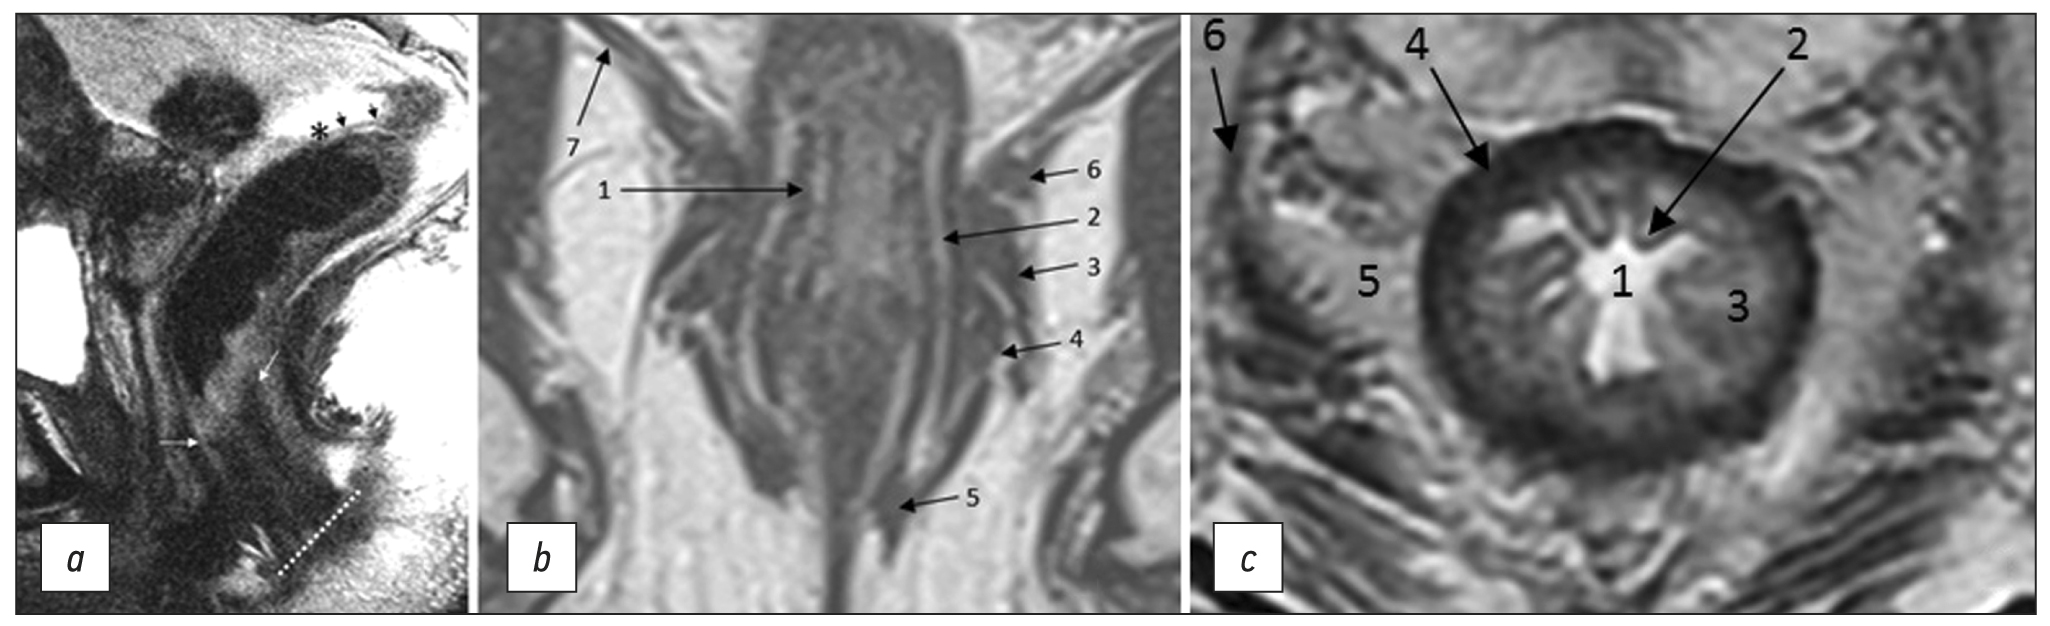

- Bogveradze N, Snaebjornsson P, Grotenhuis BA, et al. MRI anatomy of the rectum: Key concepts important for rectal cancer staging and treatment planning. Insights Imaging. 2023;14(1):13. doi: 10.1186/s13244-022-01348-8

- Santiago I, Figueiredo N, Parés O, et al. MRI of rectal cancer: Relevant anatomy and staging key points. Insights Imaging. 2020;11(1):100. doi: 10.1186/s13244-020-00890-7